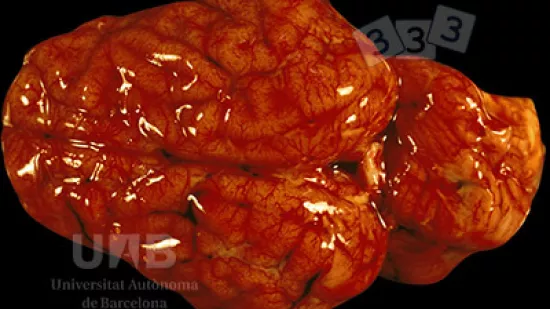

Wie lautet die Todesursache für dieses kürzlich verendete 12 Wochen alte Schwein?